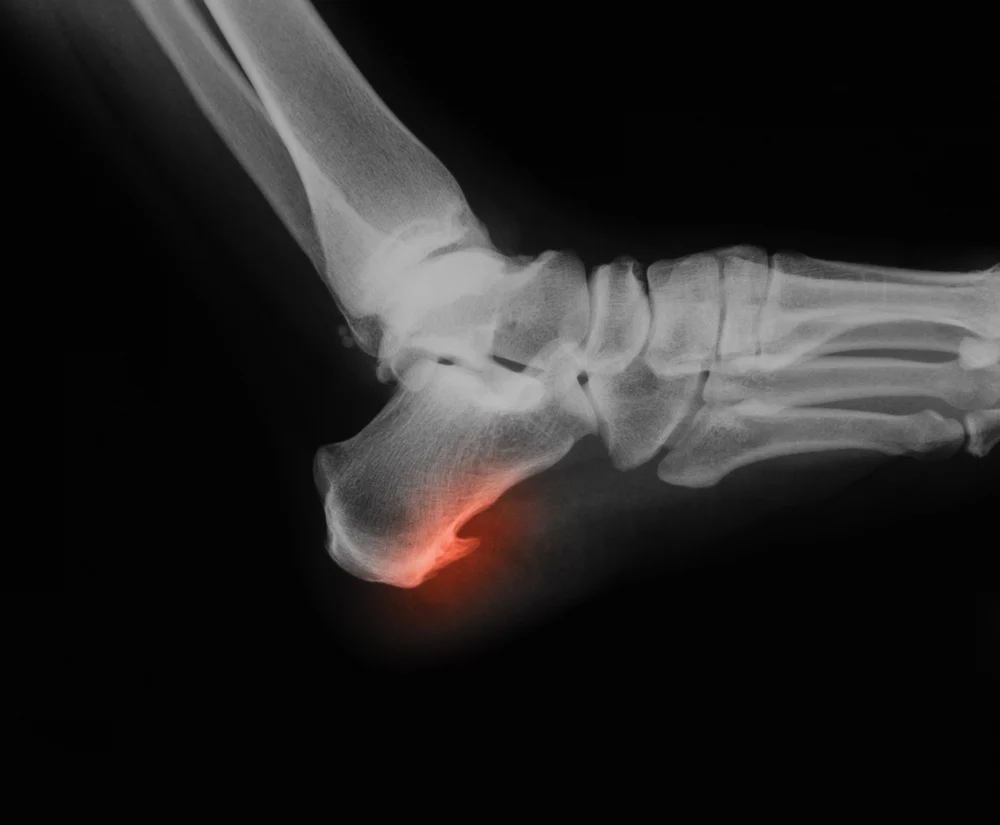

خار پاشنه،که از نظر پزشکی به عنوان رسوب کلسیم در زیر استخوان پاشنه (استخوان کالکانئوس) شناخته می شود، اغلب نتیجه کشیدگی و التهاب طولانی مدت رباط کف پا (فاسیا پلانتار) است. این رباط از پاشنه تا انگشتان پا کشیده شده و نقش حیاتی در حمایت از قوس کف پا ایفا می کند. فشار مکرر،پوشیدن کفش نامناسب، اضافه وزن،ناهنجاری های پا و ایستادن طولانی مدت می تواند به این رباط آسیب رسانده و در نهایت منجر به تشکیل خار پاشنه و التهاب مزمن در ناحیه اتصال آن به استخوان پاشنه شود.

اهمیت تشخیص و درمان تخصصی: برای درمان مؤثر و ریشه ای،مراجعه به متخصصین ارتوپدی و فیزیوتراپی ضروری است. تشخیص دقیق با معاینه بالینی و در صورت لزوم تصویربرداری (مانند عکسبرداری اشعه ایکس) اولین گام است. سپس، متخصصین می توانند برنامه درمانی شخصی سازی شده ای را ارائه دهند.